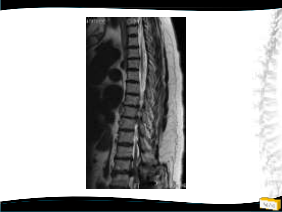

• 48y, K

• Pilates

Öğretmeni

• Şiddetli bel ağrısı

Tedavi ?

Düzey III Tedavi

– Konservatif

– Cerrahi

• Teknik?

Yapılan Ameliyat

• T12-L5 tp fiksasyon

• L4 laminektomi ile L3-L4 ve L4-L5 mesafelerinin dekompresyonu

• Posterolateral grefleme

• 3 yıllık takipte sorunsuz